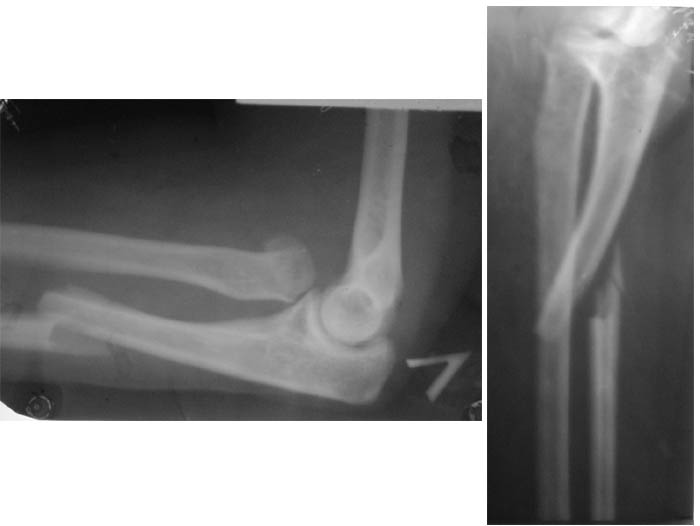

Уважаемые коллеги! Больная, 28 лет. Сутки назад получила травму (см.), сопут. - эпилепсия (инвалид 2 группы с 16 лет).

Перелом Монтеджи. Лечить следует оперативно, консервативная тектика при такой травме неприменима из-за повреждения связки на головке лучевой кости и невозможности удержания её консервативными методами. Необходим остеосинтез локтевой кости (штифт, пластина) и резекция головки лучевой кости.

Во-первых повреждение Монтеджи плюс перелом шейки лучевой кости.Возможна первичная закрытая репозиция с фиксацией головки и шейки спицей через головочку мыщелка с послед. фиксацией гипс. лонгетой.При неудаче отсроченная открытая репозиция головки луч. кости с фиксацией спицей, если не произошла репозиция локт. кости, открытый остеосинтез кости пластиной.Резецировать головку по данной рентгенограмме нет необходимости, хотя окончательное решение нужно принимать интраоперационно.